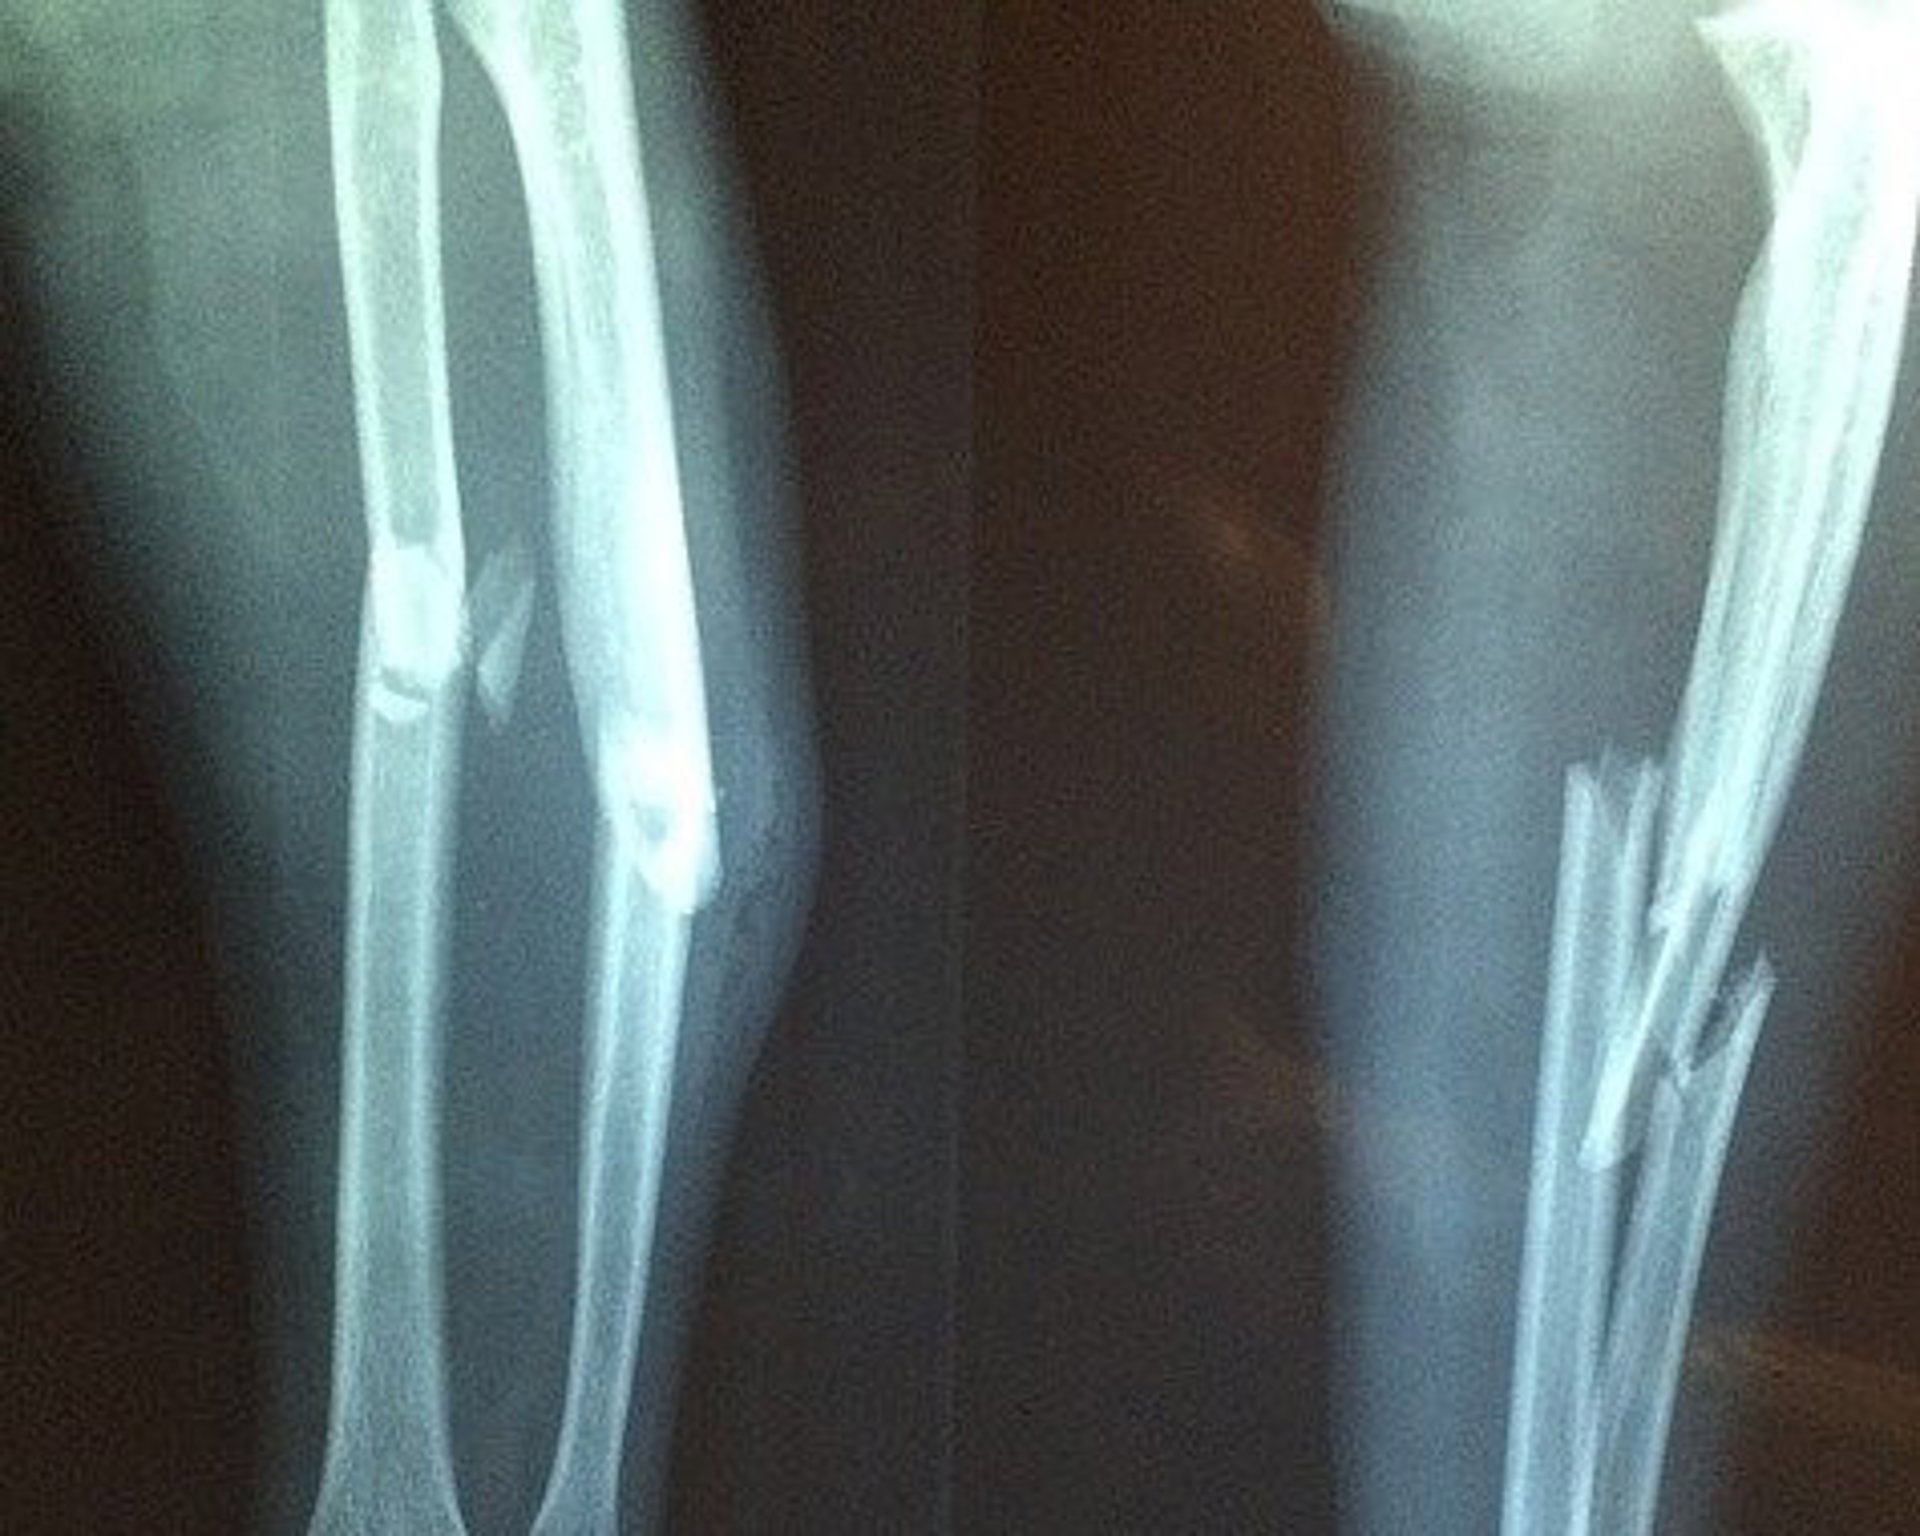

Archivo - Fractura hueso, hueso roto

Archivo - Fractura hueso, hueso roto - TAOKINESIS/PIXABAY - Archivo